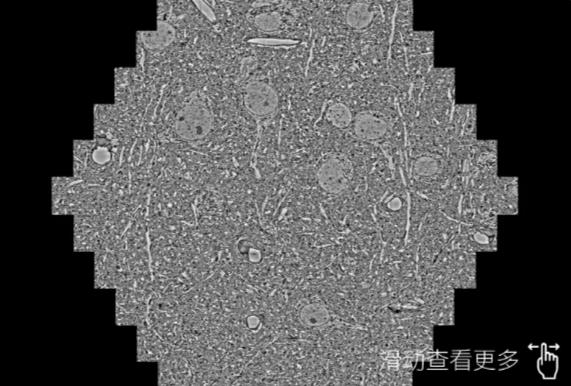

鼠脑切片。左图使用日照蔡司日照扫描电镜MultiSEM706对165μmx143pm面积区域成像,耗时仅需1.5秒。右图为鼠脑切片中30μm区域放大效果。样品由芝加哥大学B.Kasthuri提供。